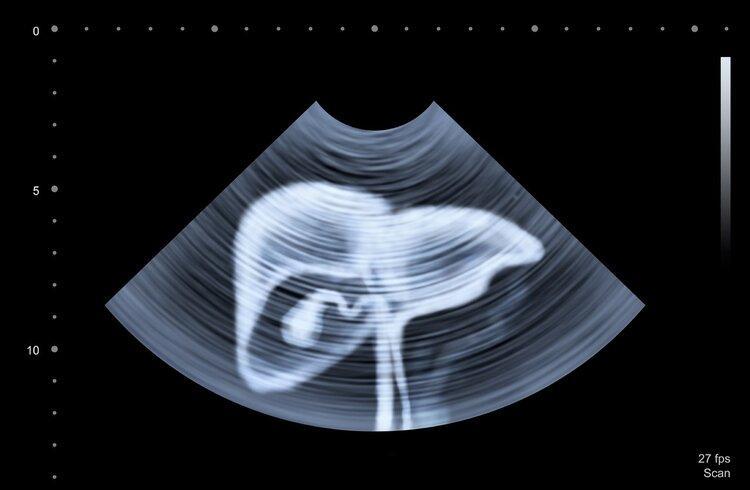

6.肝癌

肝癌早期篩查手段主要是肝臟彩超、血清甲胎蛋白(AFP)檢查,年齡在40歲及以上,有肝硬化病史或HCV慢性感染的人屬於肝癌高危風險人羣,建議定期篩查。